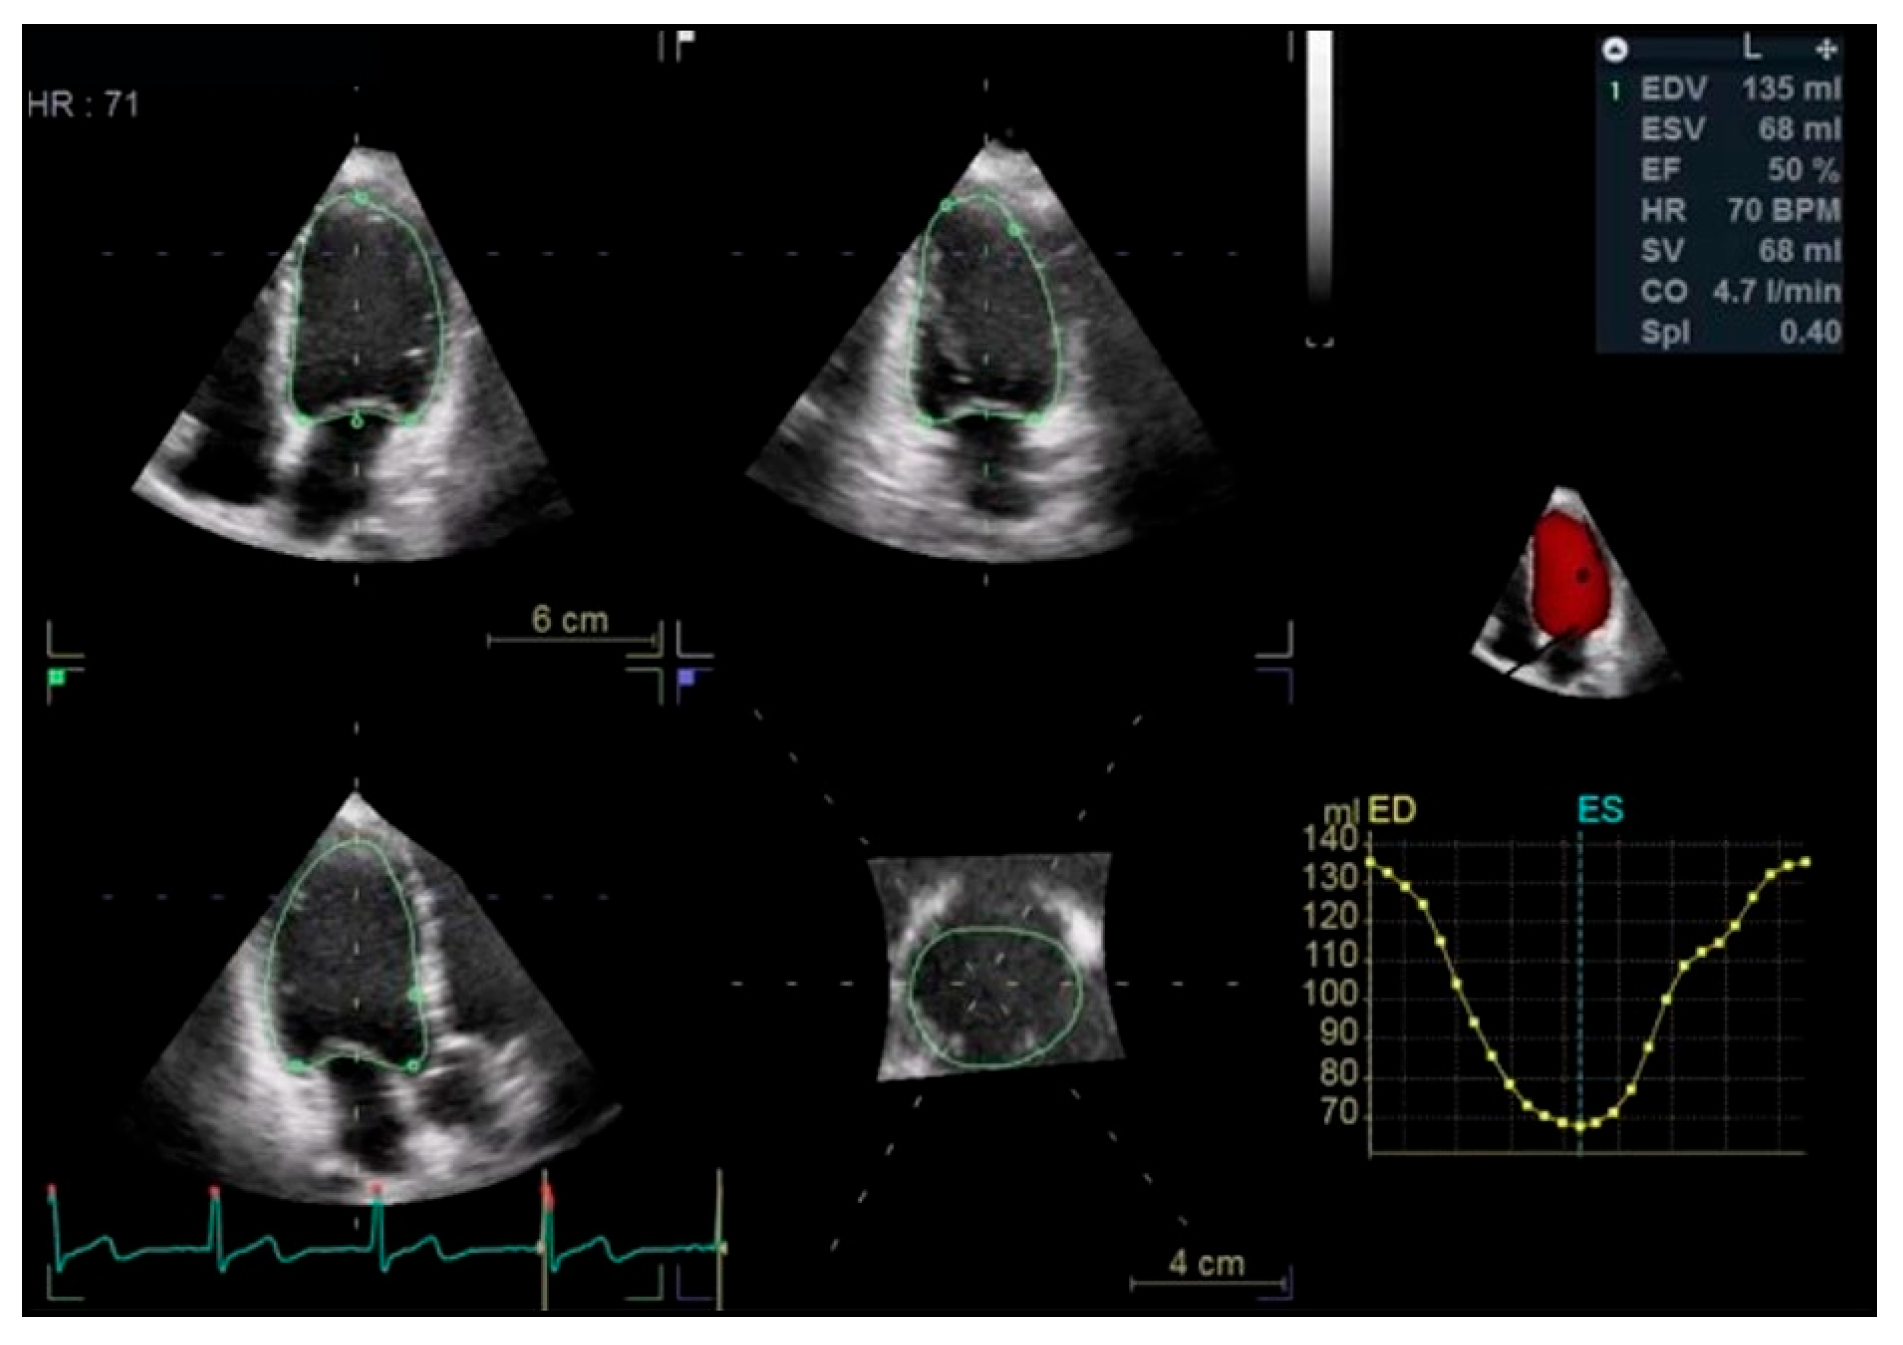

Left Ventricular Systolic Function

- CAIANI, E. Improved Semiautomated Quantification of Left Ventricular Volumes and Ejection Fraction Using 3-Dimensional Echocardiography with a Full Matrix-Array Transducer: Comparison with Magnetic Resonance Imaging. J. Am. Soc. Echocardiogr. 2005, 18, 779–788. [Google Scholar] [CrossRef] [PubMed]

- Mor-Avi, V.; Jenkins, C.; Kühl, H.P.; Nesser, H.-J.; Marwick, T.; Franke, A.; Ebner, C.; Freed, B.H.; Steringer-Mascherbauer, R.; Pollard, H.; et al. Real-Time 3-Dimensional Echocardiographic Quantification of Left Ventricular Volumes. JACC Cardiovasc. Imaging 2008, 1, 413–423. [Google Scholar] [CrossRef] [PubMed]

- Thavendiranathan, P.; Grant, A.D.; Negishi, T.; Plana, J.C.; Popović, Z.B.; Marwick, T.H. Reproducibility of Echocardiographic Techniques for Sequential Assessment of Left Ventricular Ejection Fraction and Volumes. J. Am. Coll. Cardiol. 2013, 61, 77–84. [Google Scholar] [CrossRef]